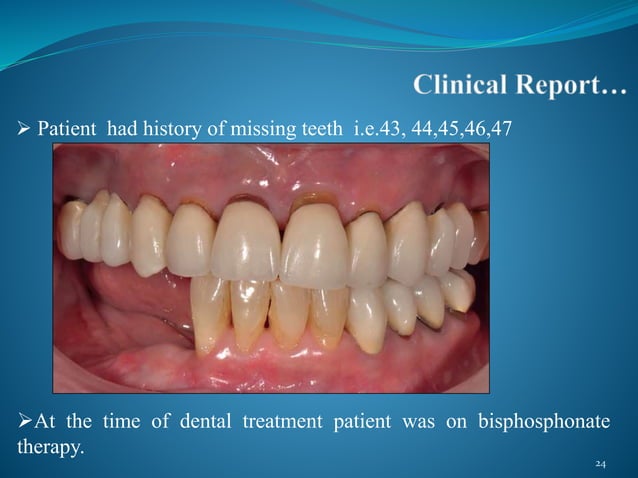

Clinical Characteristics Of An Allergic Reaction To A Polyether Denta…

www.slideshare.net

www.slideshare.net

allergic reaction impression polyether clinical

Clinical Characteristics Of An Allergic Reaction To A Polyether Dental

www.thejpd.org

www.thejpd.org

impression polyether allergic reaction mucosa preoperative

Clinical Characteristics Of An Allergic Reaction To A Polyether Dental

www.slideshare.net

www.slideshare.net

Clinical Characteristics Of An Allergic Reaction To A Polyether Dental

www.slideshare.net

www.slideshare.net

Clinical characteristics of an allergic reaction to a polyether dental. Clinical characteristics of an allergic reaction to a polyether dental. Clinical characteristics of an allergic reaction to a polyether dental